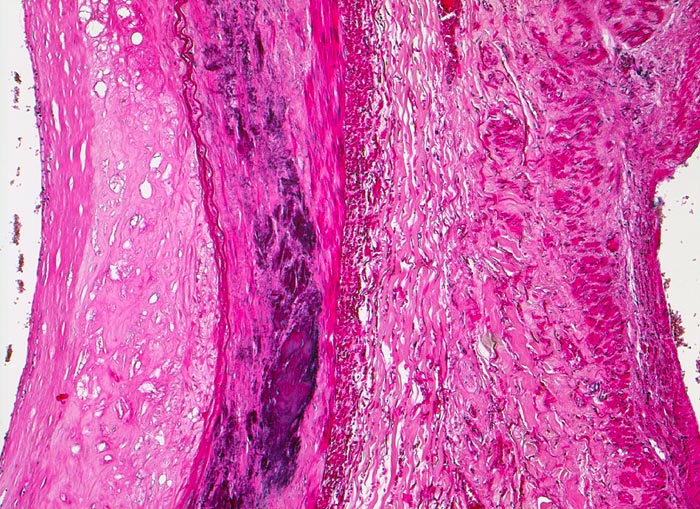

Atherosklerose

Arteria poplitea

Links im Bild die Arteria poplitea mit fibrosierter und verdickter Intima mit herausgelösten Cholesterinkristallen. Lamina elastica interna an der Grenze zur atrophen und verkalkten Media. Rechts im Bild unauffällige Venenwand.

Ältere Venenthrombosen sind aufgrund der Organisation wandhaftend.